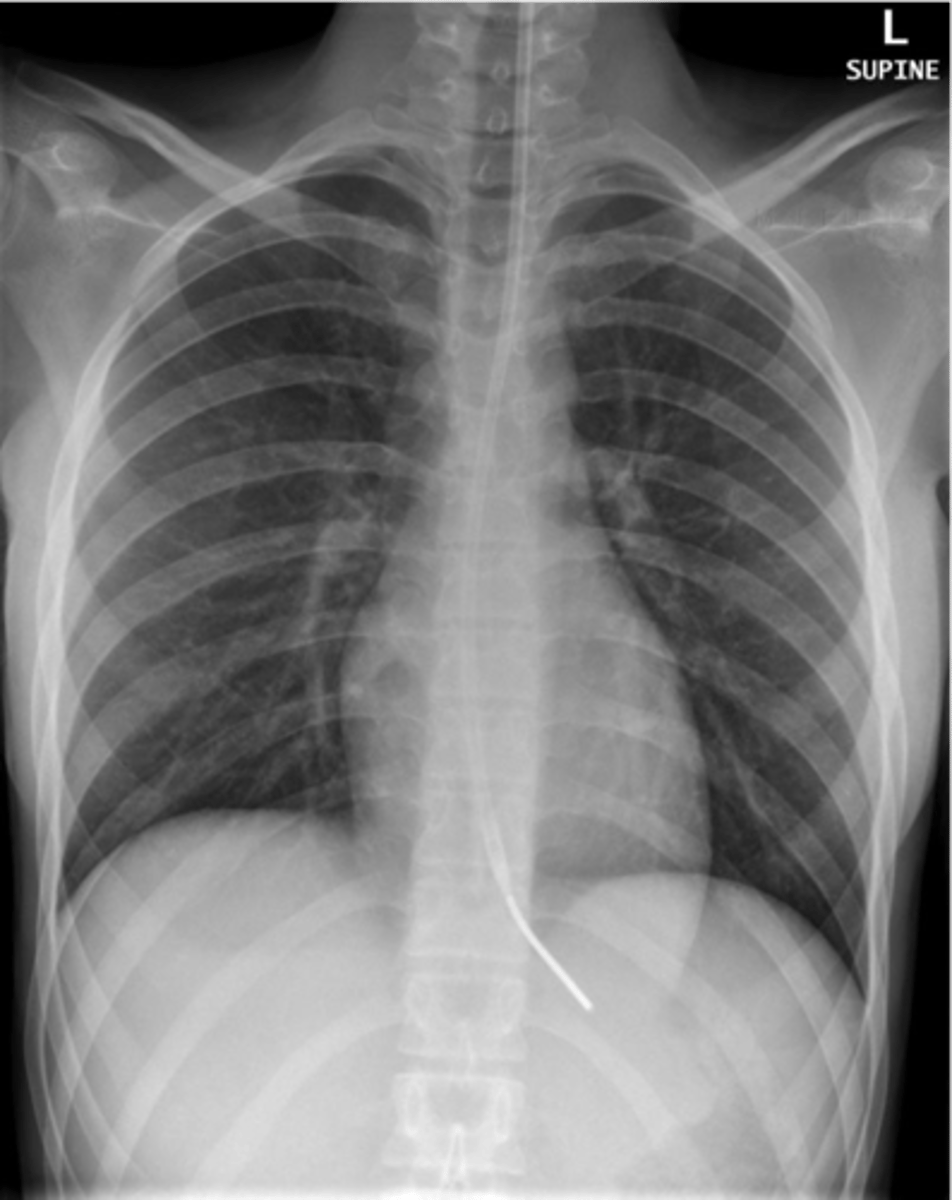

-effusion: tip posteriorly and inferiorly

-pneumothorax: tip anteriorly and superiorly

Chest tube

-tip in SVC

Central venous catheter

-hard to see

peripherally inserted central catheters

-2cm from hilum in proximal pulmonary artery

swan ganz catheter